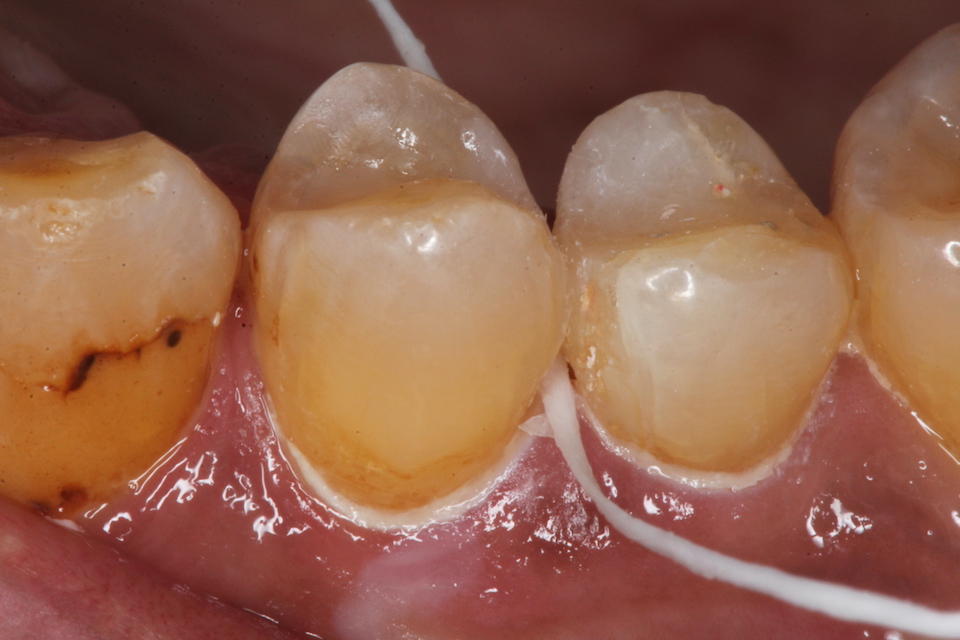

50代男性、右上45、インレー破折後の2次カリエス、咬合性外傷

露髄ギリギリなのだが、自覚症状はない。虫歯がある程度進むと染みたり痛みを感じにくくなる。それは虫歯は水素イオンの電導性がないからだ。水素イオンが歯髄の神経に到達すると痛みを感じるのだが、水素イオンの伝導は歯の主成分のハイドロキシアパタイトだけにしか起こらず、ハイドロキシアパタイトが壊れてしまった虫歯には水素イオンが伝導しない。

内部の象牙質はほぼ失われているので、全体が壊れるのは時間の問題だ。なぜならエナメル質は硬いが脆いので仮りに修復したとしても咬合性外傷がある限り、今度は根元から破折する可能性は高い。

咬合性外傷による虫歯が疑われるので、ナイトガードを診断用に使っていただくことにした。昼間も食いしばっているらしいので、作業中も使っていただくことを指示しました。2、3ヶ月使って画像を送っていただくことにしましたので、分かりやすかったらアップ予定。

咬合性外傷があるとスレあとが着く。